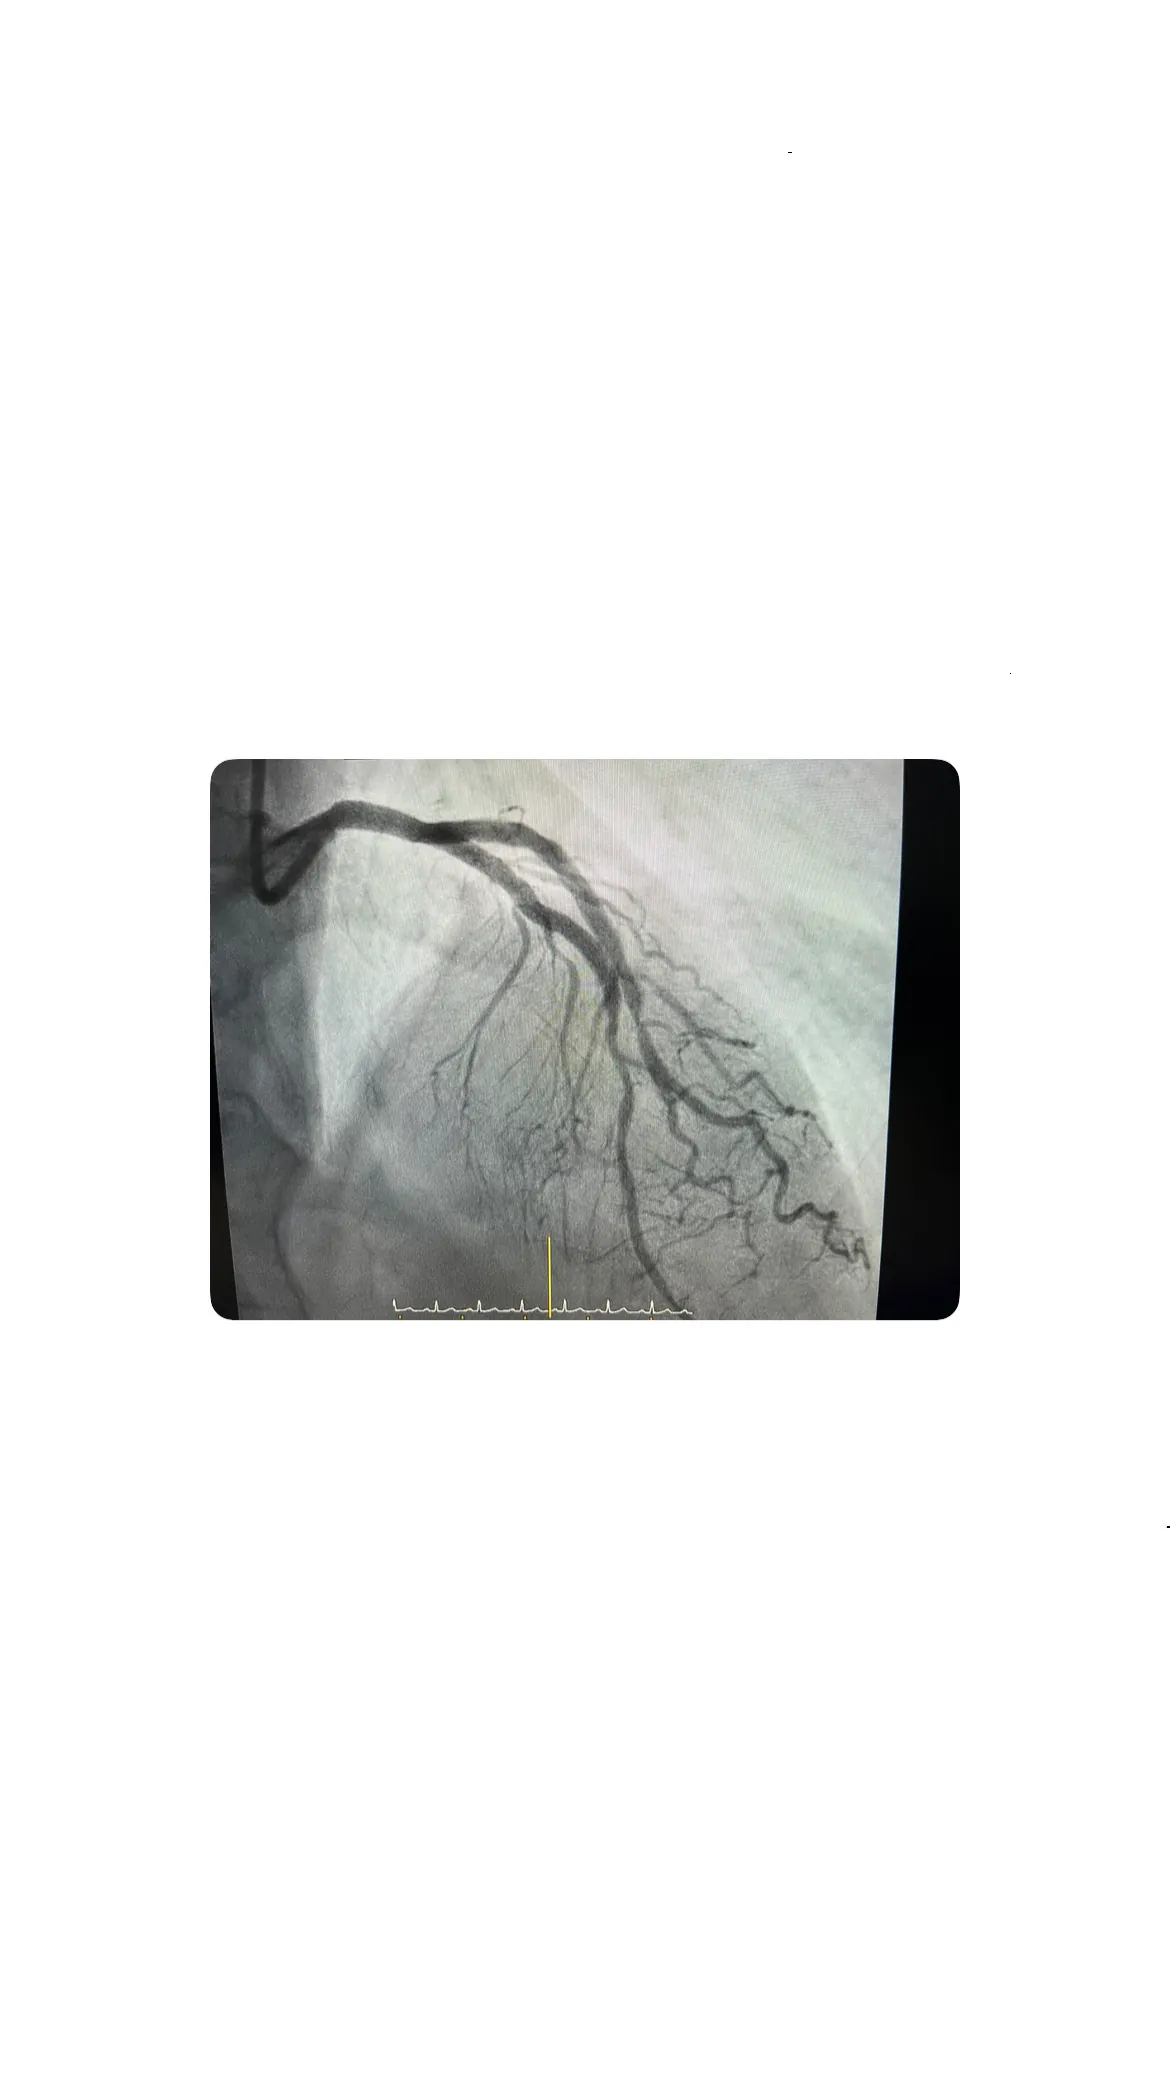

Acceso radial derecho y exploración coronaria

El acceso radial derecho es una técnica comúnmente utilizada en cateterismos debido a su menor riesgo de complicaciones y rápida recuperación. En este caso, se optó por este acceso para explorar las arterias coronarias del paciente. Durante la exploración, se observó que la coronaria derecha no presentaba lesiones significativas, lo que permitió centrar la atención en la coronaria izquierda, donde se detectó una posible lesión severa.

Coronaria derecha sin lesiones significativas

La exploración de la coronaria derecha reveló que no había lesiones significativas, lo que fue un alivio inicial para el equipo médico. Esto significaba que, al menos en esta arteria, no había riesgo inmediato de obstrucción. Sin embargo, la ausencia de problemas en la coronaria derecha no descartaba la posibilidad de complicaciones en otras áreas, por lo que la atención se dirigió a la coronaria izquierda.